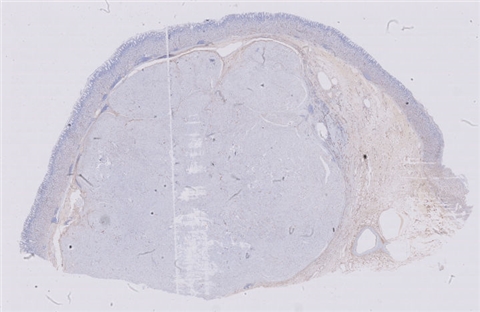

性别:       年龄:10

患者详情: 主诉:视物模糊1月余,发现抽搐、双下肢活动障碍、声音嘶哑10余天。 10-6 CT示腹膜后不规则软组织占位; 10-16彩超示腹主动脉周边前侧肾动脉平面可见一大小约为44*48*25mm的低回声团块,临近腹主动脉,边界尚清晰,形态欠规则,内部回声不均匀,未及明显钙化及液性暗区。

大体所见: 结节状组织一个: 4. 2cm*3cm*2.3cm,切面灰红灰黄。

免疫组化: NSE(3+)、Syn(3+)、CgA(3+)、CD99胞质(+)、WT-1(+)、INI-1(+)、CK广谱(-)、CD10(-)、TFE3(-)、Inhibina(-)、HMB45(+)、CD56(3+)、TLE1(-)、S-100(+)、Pax-8(+)、calretin(-)、Alk(-)、Fil-1(-)、CyclinD1(-)